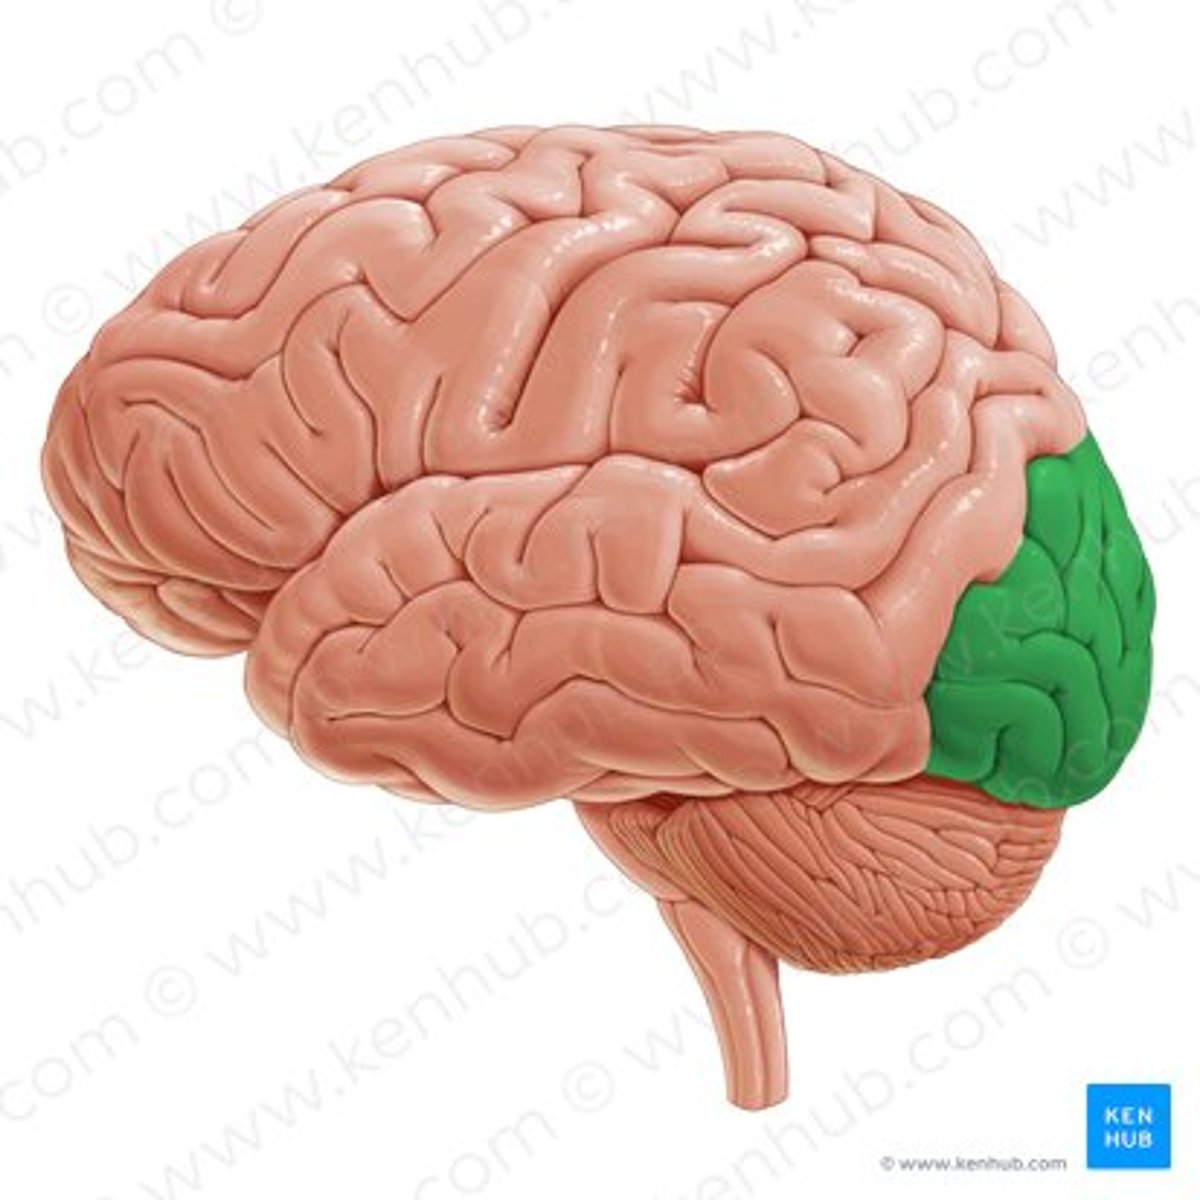

occipital lobe